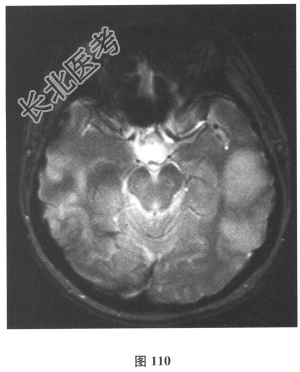

- 简答题2、脑脊液检查:常规、生化均正常,CSF-病毒TORCH(-),抗Hu、Yo、Ri均阴性,OB、MBP正常。血清抗Hu、Yo、Ri均阴性。颅脑MRI显示左颞枕、右顶枕多发长T₁、长T₂信号,Flair高信号,病变累及皮质及皮质下白质,病灶无强化,见图108~图114。根据颅脑MRI,需要鉴别的疾病应是